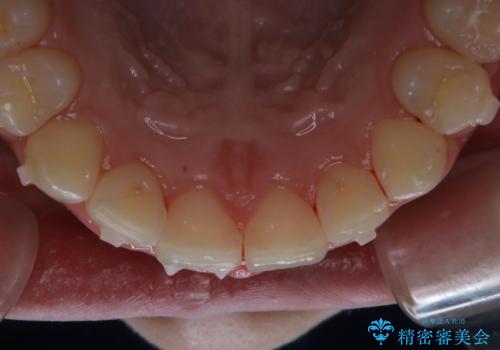

インビザライン中にステインの除去

- インビザラインでのマウスピース矯正中の方で、歯の表面のステインをきれいに取りたいとのことでした。PMTC60分コースを行いました。

PMTC(保険外治療)は、毎日の歯磨きで落としきれない汚れや、コーヒ、紅茶・タバコのヤニなどの着色も除去します。目には見えない歯と歯の間・歯肉の境目・インビザライン中はアタッチメント周囲などに残っているプラーク(歯垢)もしっかり取り除きます。PMTCでは専門的な機械や材料を使用して、徹底的に汚れを除去するため、虫歯・歯周病・口臭予防などにつながります。

またPMTCを行うことで、ご自身本来の歯の色になり自然な明るさになります。